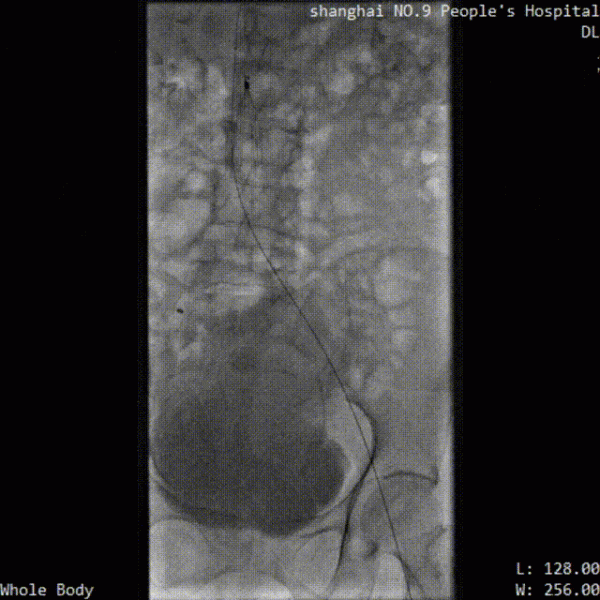

※ 取栓手術血栓清除情況: